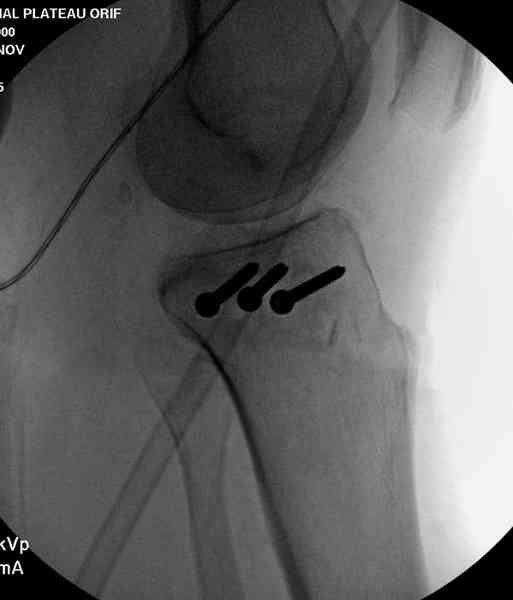

Из медиального окна можно приподнять латеральную

импрессию. Фиксация тремя параллельными шурупами в

эпифизарной части над импрессией. Создается крыша,

которая предупредит коллапс. На образовавшуюся полость - костная пластика из аутокости или синтетический заменитель. Мы применяем Osteoset в 4-5 мм диаметре таблеточки или иньекционную форму Prodens.

Нет, малоберцовый внизу, фиксацию проводим на верхнем эпифизе, где твердая кость. Задача состоит

в том, чтобы создать арматуру из нескольких проведенных шурупов на эпифизе.

Медиально, обычно на протовоположной

строне, делается окно в кортикальном слое, кривым забойником под рентгеном поднимается импрессия.

После заполнения образовавшейся полости в метафизе

кортикальное окно можно прикрыть.